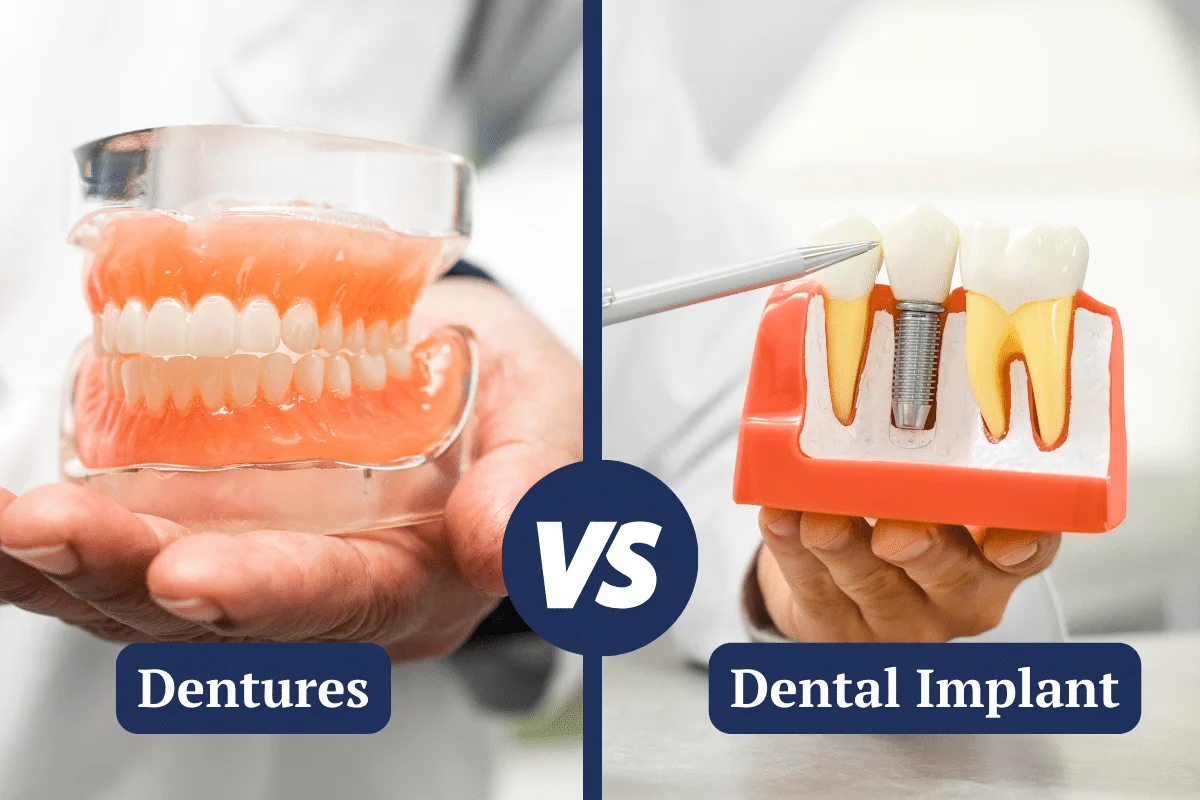

ایمپلنت دندان بهتر است یا دندان مصنوعی؟ از دست دادن دندان یکی از مشکلات شایعی است که میتواند بر سلامت...